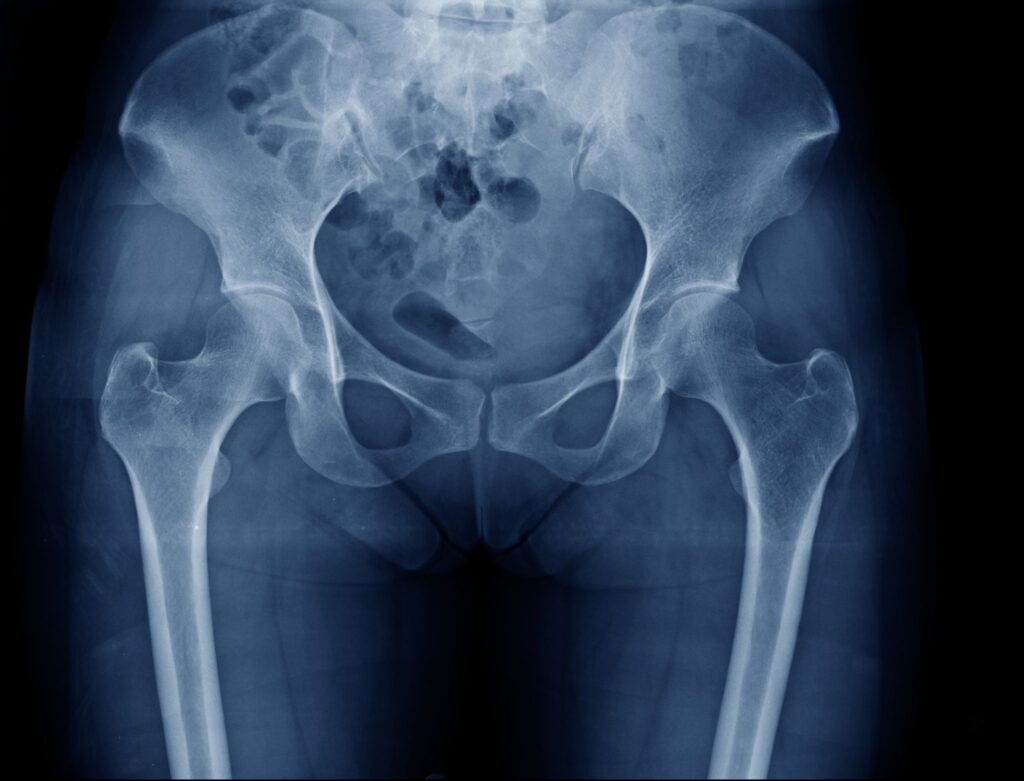

2. レントゲン検査

レントゲン検査

股関節の骨や関節の状態を確認するために、レントゲン検査を行います。骨折や腫瘍などが疑われる所見がないかも併せて確認します。